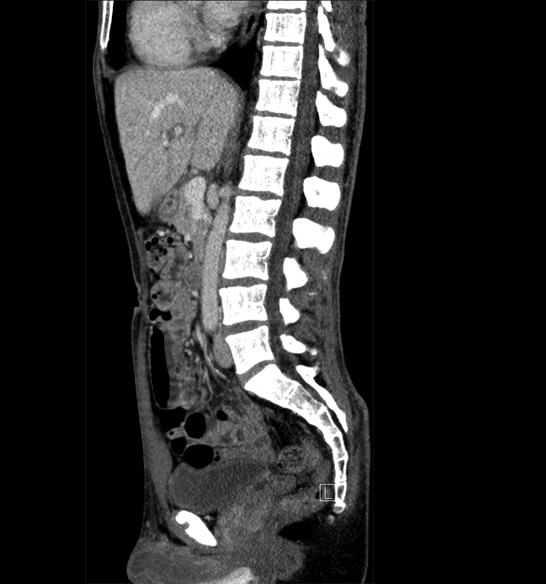

Body

Covers abdominal CT anatomy.